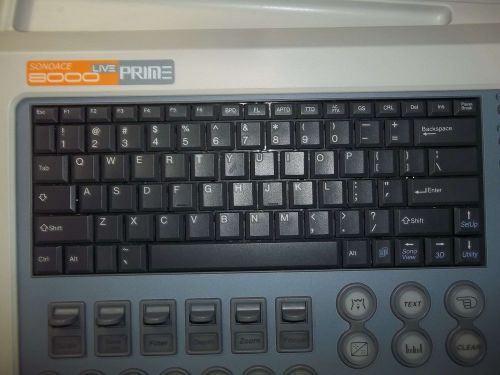

Medison SonoAce 8000 EX Ultrasound System